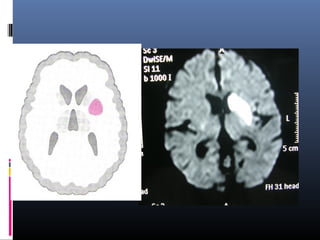

DIFFUSION MRI

 Is uniquely sensitive to detect earliest changes

within 90 mins

 Sen88% -100% sp 86-100%

 Acute stages - infarcted tissue has low ADC & seen

as hyperintense on DW1

 Chr infarcts are hypointense on DW1 & hyperintense

on ADC

ADVANTAGES OF DWI OVER CONVENTIONAL

MRI

1. Identify stroke before conventional imaging.

2.Differentiate acute from chronic infarcts

3. Show small lesions adjacent to CSF (also be

diagnosed by FLAIR)

4.Fresh lesion can be identified among multiple

infarcts

5. To help predict outcome and to facilitate

correlation with final infarcts size

MRI Ischemia Timecourse

T2

DWI

ADC

In the acute phase T2WI will be

normal, but with time the

infarcted area will become

hyperintense.

The hyperintensity on T2WI

reaches its maximum between 7

to 30 days. After this it starts to

fade.

DWI is already positive in the

acute phase and then becomes

more bright with a maximum at 7

days.

DWI in brain infarction will be

positive for approximately for 3

weeks after onset (in spinal cord

infarction DWI is only positive for

one week!).

ADC will be of low signal

intensity with a maximum at 24

hours and then will increase in

signal intensity and finally

becomes bright in the chronic

stage.